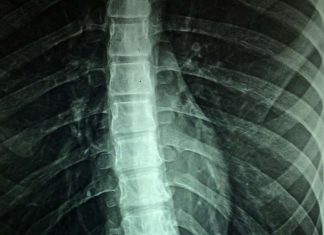

Research: New artificial neural network detects radiographic sacroiliitis with accuracy

New research presented this week at ACR Convergence, the American College of Rheumatology’s annual meeting, found that an innovative new artificial neural network can...